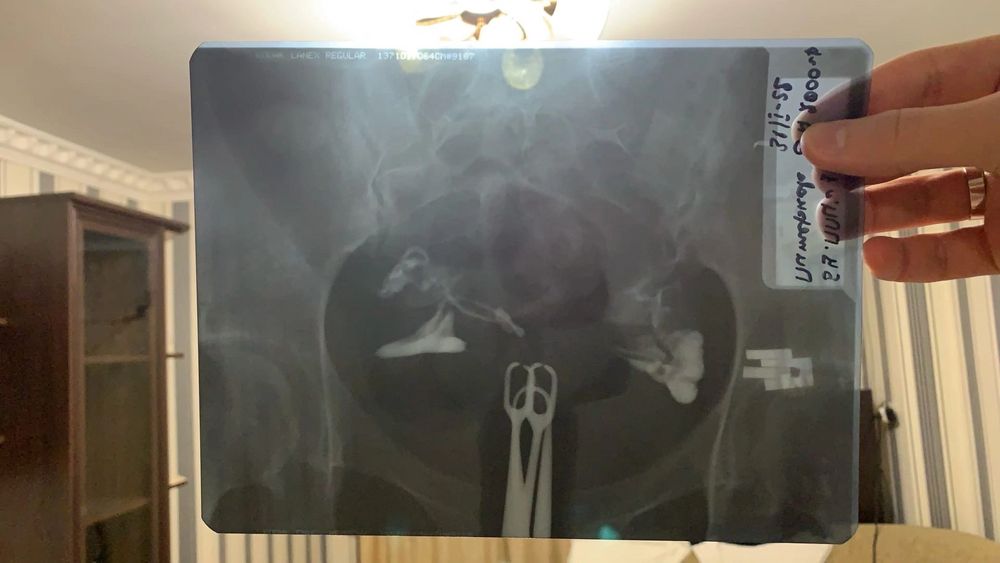

Гсг рентген

Добрый день ,проходила процедуру гсг рентген ,была фолликулярная киста которая рассасывалась ,в правой трубе скопление жидкости и она расширена но проходима полностью ,левая проходима частично ,скажите пожалуйста может это из за кисты скопление жидкости ? 2 врача говорят по разному хотелось ещё мнения послушать .прикрепляю фото рентгена и заключение